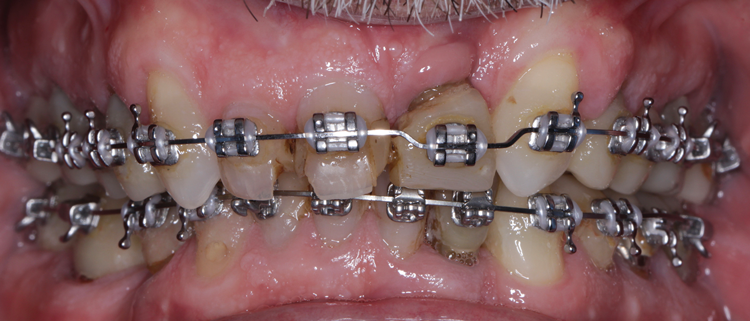

(7.) Pretreatment retracted view of a 60-year-old male patient who presented to receive comprehensive care and full-mouth rehabilitation to enhance his function, stability, and esthetics. Due to his malocclusion at the time of presentation, adult orthodontic treatment was recommended. Given the patient’s anterior deep vertical overlap, the decision was made to temporarily challenge his vertical dimension of occlusion to facilitate ease of bracketing the mandibular anterior teeth. This was to be achieved with posterior full-coverage composite crowns.

Figure 7